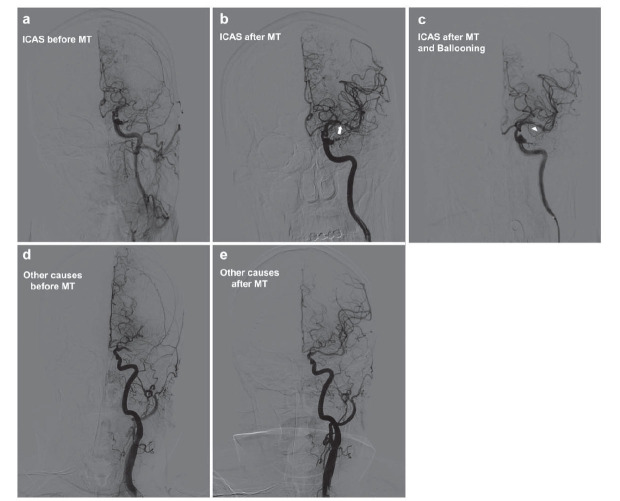

Methods: A retrospective analysis was conducted on 224 AIS patients who underwent endovascular therapy (EVT) at one single Chinese Stroke Center between April 2022 and December 2023. Clinical and radiological data were collected, including patients' demographics, CTP parameters, and 90-day modified Rankin Scale (mRS) scores. Logistic regression and receiver operating characteristic (ROC) curves evaluated the predictive power of CTP parameters for ICAS.

Results: CTP analysis revealed significant differences in perfusion parameters between ICASinduced AIS and other etiologies. ICAS patients had a smaller ischemic volume on admission and higher mismatch ratios [Time to Maximum, Tmax>6s: Other Causes: 132.4 [70.5, 183.3] mL, ICAS: 96.3 [79.8, 107.3] mL, p =0.0064; relative cerebral blood flow, rCBF<30%: Other Causes: 2.4 [0.0, 10.8] mL, ICAS: 0.6 [0.0, 7.0] mL, p =0.0145; mismatch ratio: 7.4 [2.5, 15.0], ICAS: 11.0 [4.6, 17.8], p =0.0285], indicating more salvageable brain tissue. The 90-day mRS showed better functional outcomes in the ICAS group, with a higher likelihood of minimal to no disability [mRS 90 equals 0-1: ICAS: 53.0% vs. Other Causes: 36.3%, p =0.0122]. The predictive model for ICAS, combining clinical manifestations and CTP parameters, yielded an area under the curve (AUC) of 0.7779, demonstrating good diagnostic performance.

Conclusion: CTP is a valuable diagnostic tool for ICAS-induced AIS, offering the potential for early identification and informing the decision for endovascular treatment. The positive correlation between CTP findings and patient outcomes supports its utility in clinical practice.